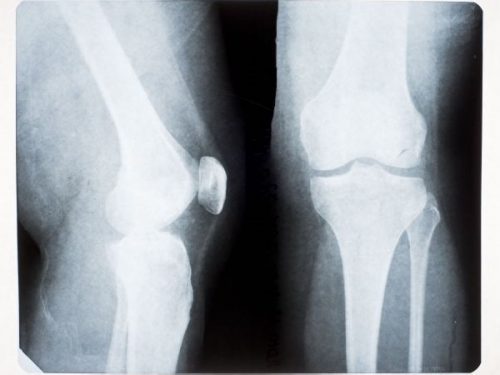

Tri naučnika sa Univerziteta u Britaniji dokazali su da je čovječanstvo tokom poslednjih 100 godina razvilo i 207. kost u organizmu. Kost se naziva fabela i smještena je sa zadnje strane zgloba koljena – a funkcija ove kosti je da čuva tetivu koja prelazi preko zgloba od oštećenja i potpomaže njene mehaničke funkcije. Rezultati njihovog istraživanja objavljeni su u Journal of Anatomy.

Do nedavno se smatralo da ovu kost ima 39% ukupne ljudske populacije, a prisutna je i kod nekih vrsta majmuna. Kao posljedica evolucije fabela je i kod majmuna i kod ljudi iščezavala, međutim, krajem 20. vijeka zabilježena je neobična pojava – fabela je kod ljudi postajala sve češće prisutna.

Podaci koje su istraživači obrađivali pokrivaju period od 1875. do 2018. godine, a zemlje koje su imale relevantne podatke i samim tim bile podneblje istraživanja su Kina, Japan, Koreja i SAD. Dok je ova kost uobičajena pojava kod drugih sisara, statistika se za ljudsku vrstu mijenjala – na primer, 1900. godine svega 7,64% ljudi je imalo ovu kost. Nakon 2000. godine procenat je skočio na 31% stanovništva u ovim zemljama. Učestalost je 3,5 puta veća, što je znak veoma brze evolucije. Danas ovu kost ima 52,83% ljudi, podjednako žena i muškaraca. Zanimljiv je podatak da 2/3 populacija ima ovu kost samo u jednom koljenu, dok 1/3 ima u oba.